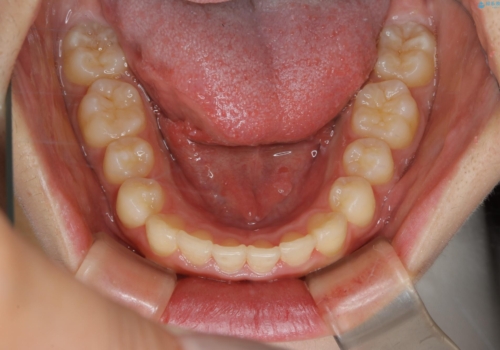

前歯のがたつきとディープバイト:インビザライン治療

- 前歯のがたつきと、噛み合わせが深いことを気にされてご相談にいらした方です。

インビザラインにて治療を行いました。

一般的に、歯冠(歯の長さ)が短い方はインビザライン治療に時間がかかりやすい傾向にあります。

歯の移動量に対して大きなブラックトライアングルもできることなく綺麗に並べることができ、大変喜んでいただけました。